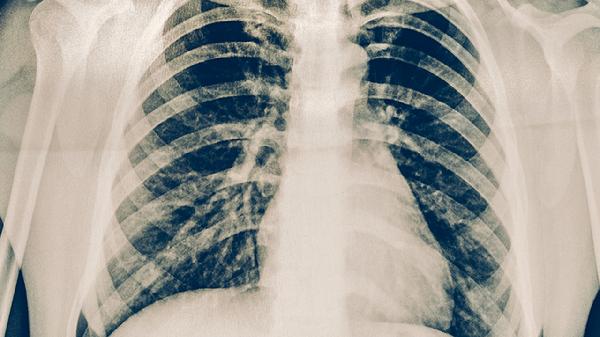

一副中藥治好肺結(jié)核

肺結(jié)核需規(guī)范抗結(jié)核治療,中藥可作為輔助調(diào)理手段,單用一副中藥無法根治。中藥調(diào)理側(cè)重滋陰潤肺、扶正祛邪,需結(jié)合體質(zhì)辨證使用。

肺結(jié)核由結(jié)核分枝桿菌感染引起,世界衛(wèi)生組織推薦標(biāo)準(zhǔn)化療方案。異煙肼聯(lián)合利福平為基礎(chǔ)用藥,配合吡嗪酰胺、乙胺丁醇等藥物,療程需6-9個(gè)月。中藥如百部、白及等雖有抑菌作用,但無法替代抗生素殺菌效果。